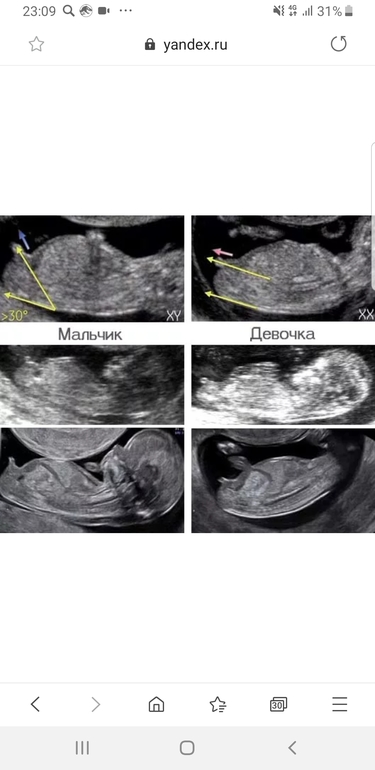

Не могу понять : на второй фото это половой бугорок или пуповина? Потому что на первой ничего не торчит ))

на втором фото точно не бугорок. мы только с первого скрининга сегодня, бугорок совсем не там. он возле выше копчика, ближе к ножкам.

На фото нельзя разобрать бугорок.. Да и не всегда работает этот метод, у меня был точно вверх бугорок, и даже в 16 недель сказали мальчик, а на 18 недели в жк сказали что жду девочку) Так что я за как можно более позднее определение пола.

Но я не могу понять где этот бугорок, не вижу его) на второй фото вроде как пуповина, потому что кажется бугорок ниже должен быть ...)

Если очень нужно это знать и не терпится, то с 10 до 12 недели можно здать кровь на определение пола) ради эксперимента в 10 нелель делала) результат 99 % пол мужской😊 так и вышло) на таком сроке женский от мужского органа отличают по углу наклона ) если на фото писюн, то похоже на мальчика)